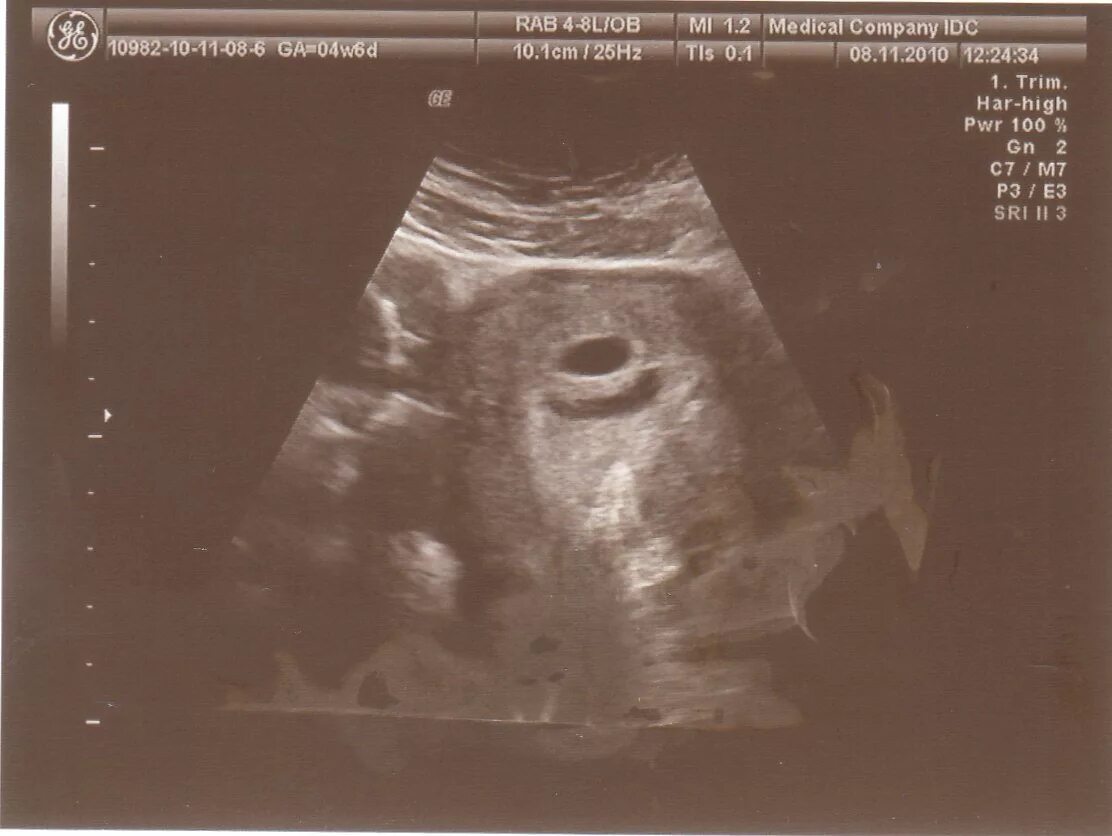

Вышла гематома форум